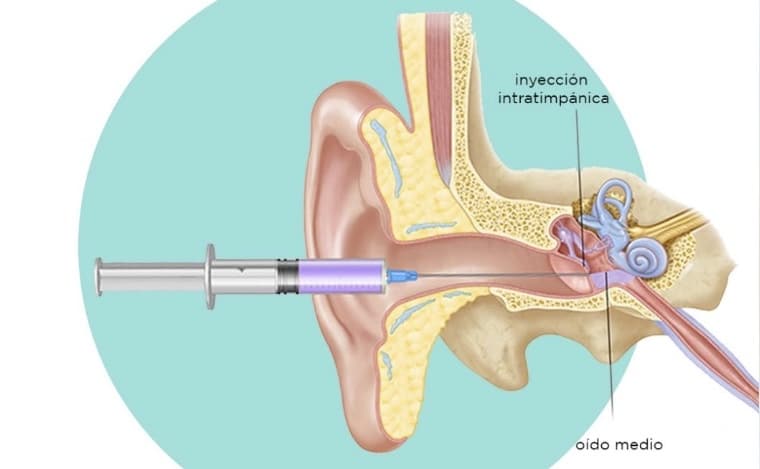

- Manejo de otitis agudas y crónicas

- Evaluación de pérdida auditiva y vértigo

Los zumbidos o tinnitus pueden ser normales ocasionalmente, pero si son persistentes, es importante acudir al especialista para descartar problemas auditivos o neurológicos.